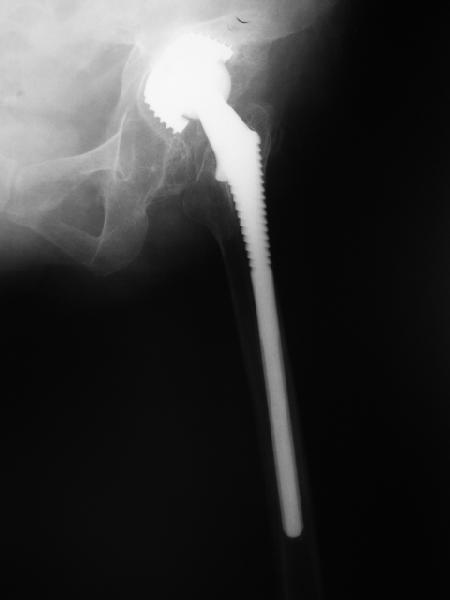

В наше отделение обратилась больная (родственница одного из сотрудников) 1948 г.р. В 2002 г. тотальное эндопротезирование тазобедренных суставов в Кургане.

Август 2002 г.

24 апреля 2005 г. правый сустав фас (тут и болит)

С выбором имплантата можно не согласиться, но скорее всего просто поставили то, что было в наличии. :( Вертлужный компонент установлен

слишком медиально. По представленным рентгенограммам нельзя исключить нарушение целостности дна вертлужной впадины. Даже если в данным момент нестабильности нет, то она обязательно возникнет и скорее всего, создаст

На представленных Р-граммах явных признаков нестабильности эндопротеза нет. Чашка хоть и медиализирована, но стоит так же, как и 3 года назад и остеолиза нет. Есть остеолиз вокруг проксималного отдела ножки, но линия тонкая и не захватывает дистальный отдел. Судя по клинике, можно думать о травме (отрыв) ягодичных мышц в